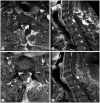

Solitary fibrous tumor is rare benign mesenchymal neoplasm. The spinal solitary fibrous tumor is extremely rare. The authors experienced a case of intramedullary solitary fibrous tumor of cervicothoracic spinal cord in a 48-year-old man with right lower extremity sensory disturbance. Spinal MRI showed intradural mass lesion in the level of C7-T1, the margin between the spinal cord and tumor was not clear on MRI. A Left unilateral laminectomy and mass removal was performed. Intra operative finding, the tumor boundary was unclear from spinal cord and it had intramedullary and extramedullary portion. After surgery, patient had good recovery and had uneventful prognosis. Follow up spinal MRI showed no recurrence of tumor.